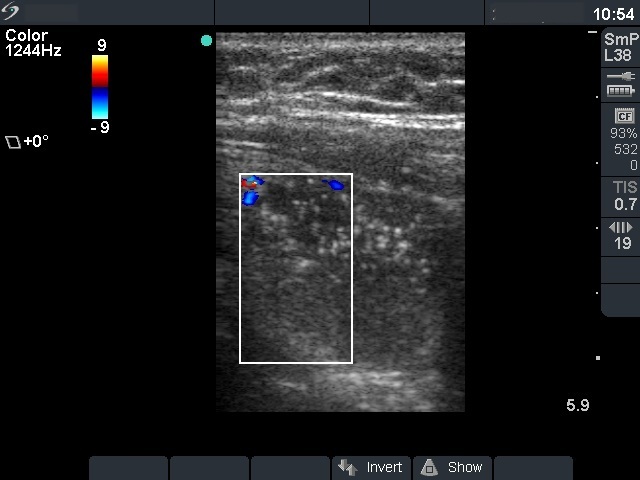

Benign nodular hyperplasia - Case 21. |

First examination (first row of images)

Clinical data: a 56-year-old man was referred for an evaluation of a recurrent nodular goiter. He was operated 14 years ago, histopathology resulted in benign, hyperplastic nodules. He had no complaints.

Palpation: a multinodular goiter.

Functional state: euthyroidism (TSH 0.69 mIU/L, FT4 12.4 pM/L).

Ultrasonography: both thyroids were enlarged and echonormal. There were multiple, moderately hypoechogenic nodules in both lobes. There was a hypoechogenic nodule in the central part of the left lobe which presented hyperechogenic patches containing bright, hyperechogenic punctate granules. This pattern is similar to that observed in medullary cancer. The vascularization was not specific.

FNAC: was repeatedly not diagnostic.